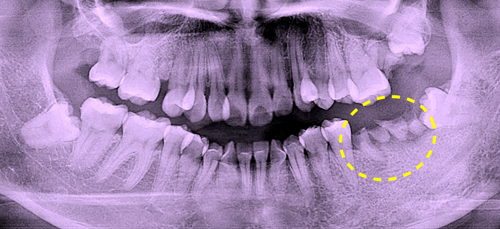

奈良の歯科医で型取りをしたまま治療放置。根の先には黒い影が発生して、大きな腫瘍が生じていると思われました。

レントゲンCT画像分析の結果、動いているのはインプラントの1本手前のご自身の歯牙であることが判明しました。

上記は、おそらく根が割れているのでは?と思われるレントゲン画像です。

抜歯の結果、根は真っ二つ割れ、根の先端には大きな膿の腫瘍が骨を溶かしている良くない状態でした。